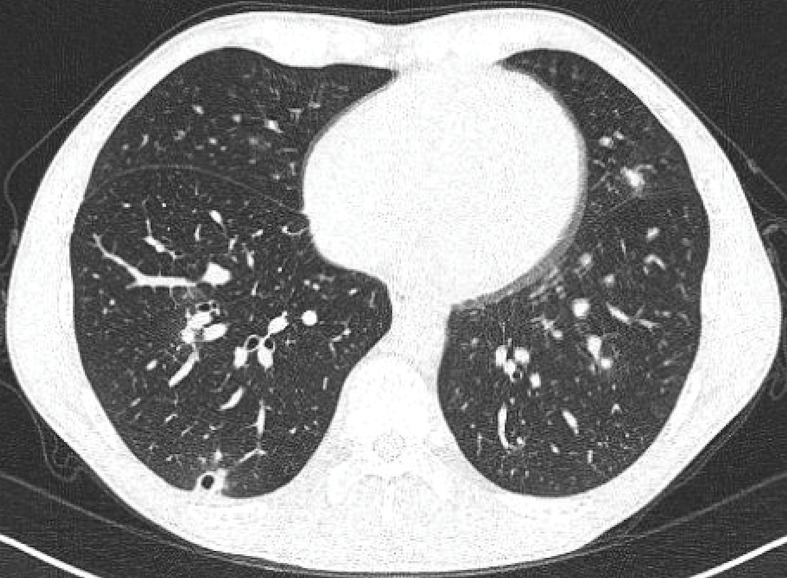

A group of four healthy Canadian travellers visited a cenote in the Yucatán peninsula in April 2024 and subsequently developed symptomatic histoplasmosis. Diagnosis was made in the acute period with a positive urine Histoplasma antigen test in three of the cases. Two developed severe presentations and were treated with itraconazole, including a three-year-old child with disseminated disease. The sensitivity of different modalities for diagnostics depends on the timing and severity of illness, with Histoplasma urine antigen being most sensitive in early infection, serology converting 4-8 weeks following exposure and cultures generally of low sensitivity. Treatment depends on the disease manifestations and host immunologic status. Many patients have relatively mild, self-limited, influenza-like illness and the diagnosis may be overlooked. Given the number of Canadian tourists travelling to the Yucatán peninsula and the popularity of visiting cenotes, awareness of the risk of histoplasmosis associated with this exposure should be promoted.